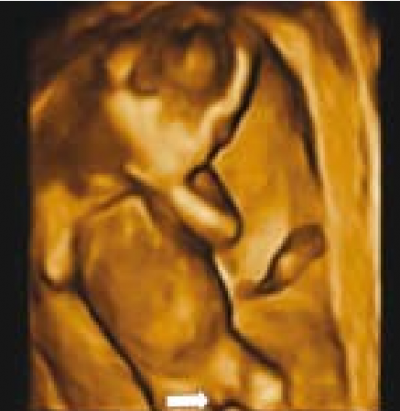

אולטרסאונד תלת ממדי - מנסיוננו, שימוש באולטרסאונד תלת ממדי אינו מוסיף משמעותית לאבחון מין העובר, במיוחד בטרימסטר הראשון ותחילת הטרימסטר השני ולעיתים יכול אפילו להטעות (תמונה 6). Benoi[9] ואחרים[31][32] הגיעו למסקנה שאכן התלת מימד אינו עוזר לאבחון מין העובר אך השימוש בחתכים (Sectional planes) לעיתים יכול לעזור על ידי הצגת החתך הסגיטלי האמצעי ביתר קלות ובכך לעזור לאבחון מין העובר. בטרימסטר השני והשלישי התלת מימד יכול לעזור בהצגת איברי המין להורים בצורה יותר משכנעת (תמונות 7 ו-8). בחלק מהמקרים עם מומים באיברי המין החיצוניים, התלת מימד יכול להדגים את המום ולעזור להגיע לאבחנה, כפי שנדון בהמשך.